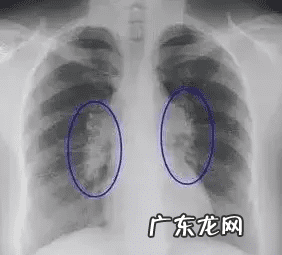

1. 肺部结节:一般年龄大、肺部有基础疾病的人,做检查易发现肺部结节 。即使发现肺部结节也不必恐慌,因为其中只有极少部分人最后被证实是肺癌 。此时必须找专业医生鉴别判断:对于小于5毫米的微小结节,仅做随访观察,3个月到半年重新做一次CT检查 。如结节没有变化、没有异常增大,一般被认为是没有风险的,有的甚至会随着时间变化慢慢消失 。1厘米以上的大结节,建议要尽早诊治 。

文章插图

肺部结节